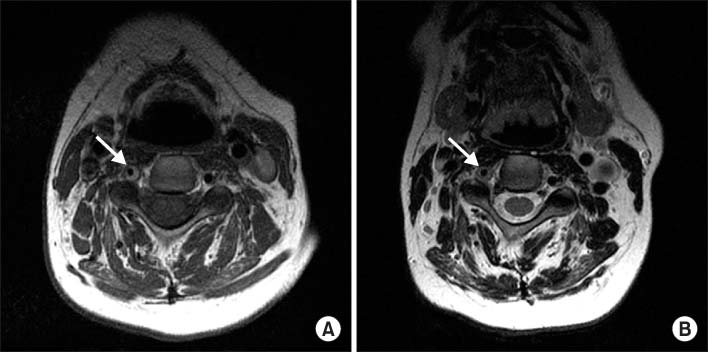

Fig. 1

(A) T1 weighted and (B) T2 weighted C-spine magnetic resonance imaging (MRI) of patient 1. Cervical MRI study shows high and isosignal intensity of the wall thickening in left vertebral artery (arrow) and combined luminal narrowing. Definite spinal cord lesion is not observed.

Fig. 1 (A) T1 weighted and (B) T2 weighted C-spine magnetic resonance imaging (MRI) of patient 1. Cervical MRI study shows high and isosignal intensity of the wall thickening in left vertebral artery (arrow) and combined luminal narrowing. Definite spinal cord lesion is not observed.